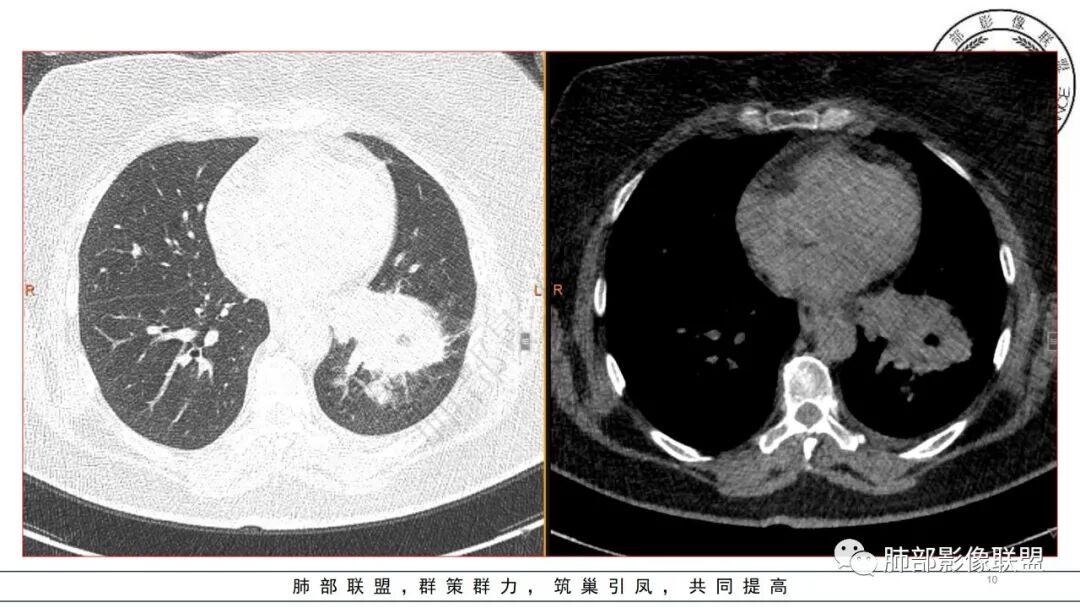

3.五天后及十三天后病灶变化明显,实性密度影吸收缩小,边界趋于清楚,显示多空腔。

有糖尿病基层,左肺大片状实变影,跨多个叶段,多次治疗复查,实变范围有缩小,部分可见空洞影,考虑肺克

糖尿病,左下肺单侧实变,多次复查可见空洞和液平面,符合坏死性肺炎,白细胞高,遗憾的是不管是前期还是复查都没给PCT值,有手术史,首先考虑肺克,鉴别金葡和大肠埃希菌